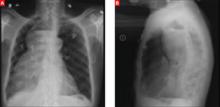

A stat CT of the patient’s abdomen and pelvis revealed no signs of obstructive uropathy to explain his acute renal failure. A sagittal CT reconstruction in bone windows of the initial ED radiological workup was revealing (FIGURE 1).

FIGURE 1

Sagittal CT reconstruction of thoracolumbar spine

The sagittal CT reconstruction in bone windows of the thoracolumbar spine (FIGURE 1) revealed multiple lucent foci throughout the osseous structures, with an anterior compression deformity of the L2 vertebral body. A subsequent skeletal survey showed a diffuse salt and pepper pattern affecting most of the osseous structures, with additional lytic lesions in the calvarium and extremities.